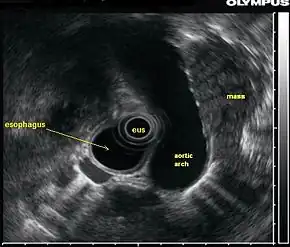

![]() In this endoscopic ultrasound image, a mass (in this case, from lung cancer) is visualized using an ultrasound probe (EUS) inserted into the esophagus. | |

Endoscopic ultrasound (EUS) or echo-endoscopy is a medical procedure in which endoscopy (insertion of a probe into a hollow organ) is combined with ultrasound to obtain images of the internal organs in the chest, abdomen and colon. It can be used to visualize the walls of these organs, or to look at adjacent structures. Combined with Doppler imaging, nearby blood vessels can also be evaluated.

An endoscopic ultrasound probe placed in the esophagus can also be used to visualize lymph nodes in the chest surrounding the airways (bronchi), which is important for the staging of lung cancer. Ultrasound can also be performed with an endoscopic probe inside the bronchi themselves, a technique known as endobronchial ultrasound.